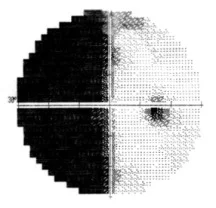

Homonymous Hemianopsia

Homonymous hemianopsia, also referred to as homonymous hemianopia is the loss of half of the field of view on the same side in both eyes. It occurs frequently in stroke, tumor and traumatic brain injuries, because of the manner in which the nasal nerve fibers from each eye cross as they pass to the back of the brain. The visual images that we see to the right side travel from both eyes to the left side of the brain, while the visual images we see to the left side in both eye travel to the right side of the brain. Therefore, damage to the right side of the posterior portion of the brain can cause a loss of the left field of view in both eyes. Likewise, damage to the left posterior brain can cause a loss of the right field of vision.